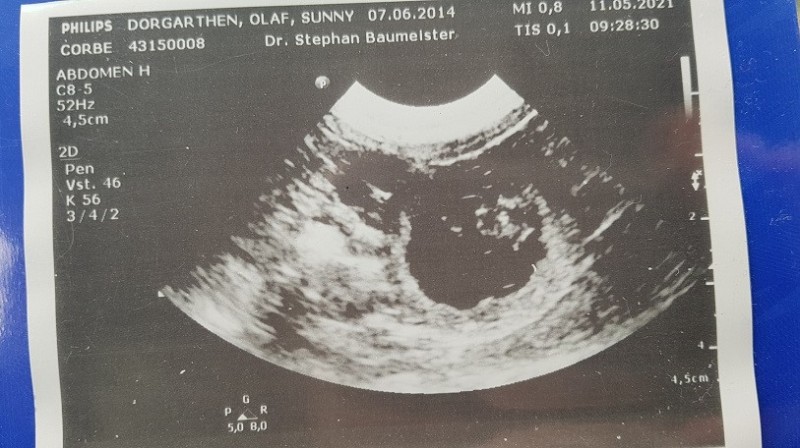

Heute am 31. Tag der Trächtigkeit waren wir beim Ultraschall. Ich war mir im Vorfeld ziemlich sicher dass das Date mit Moe erfolgreich war...Sunny zeigte mir alle, für mich eindeutige Anzeichen einer Trächtigkeit und hier die Bestätigung.

• Ultraschall